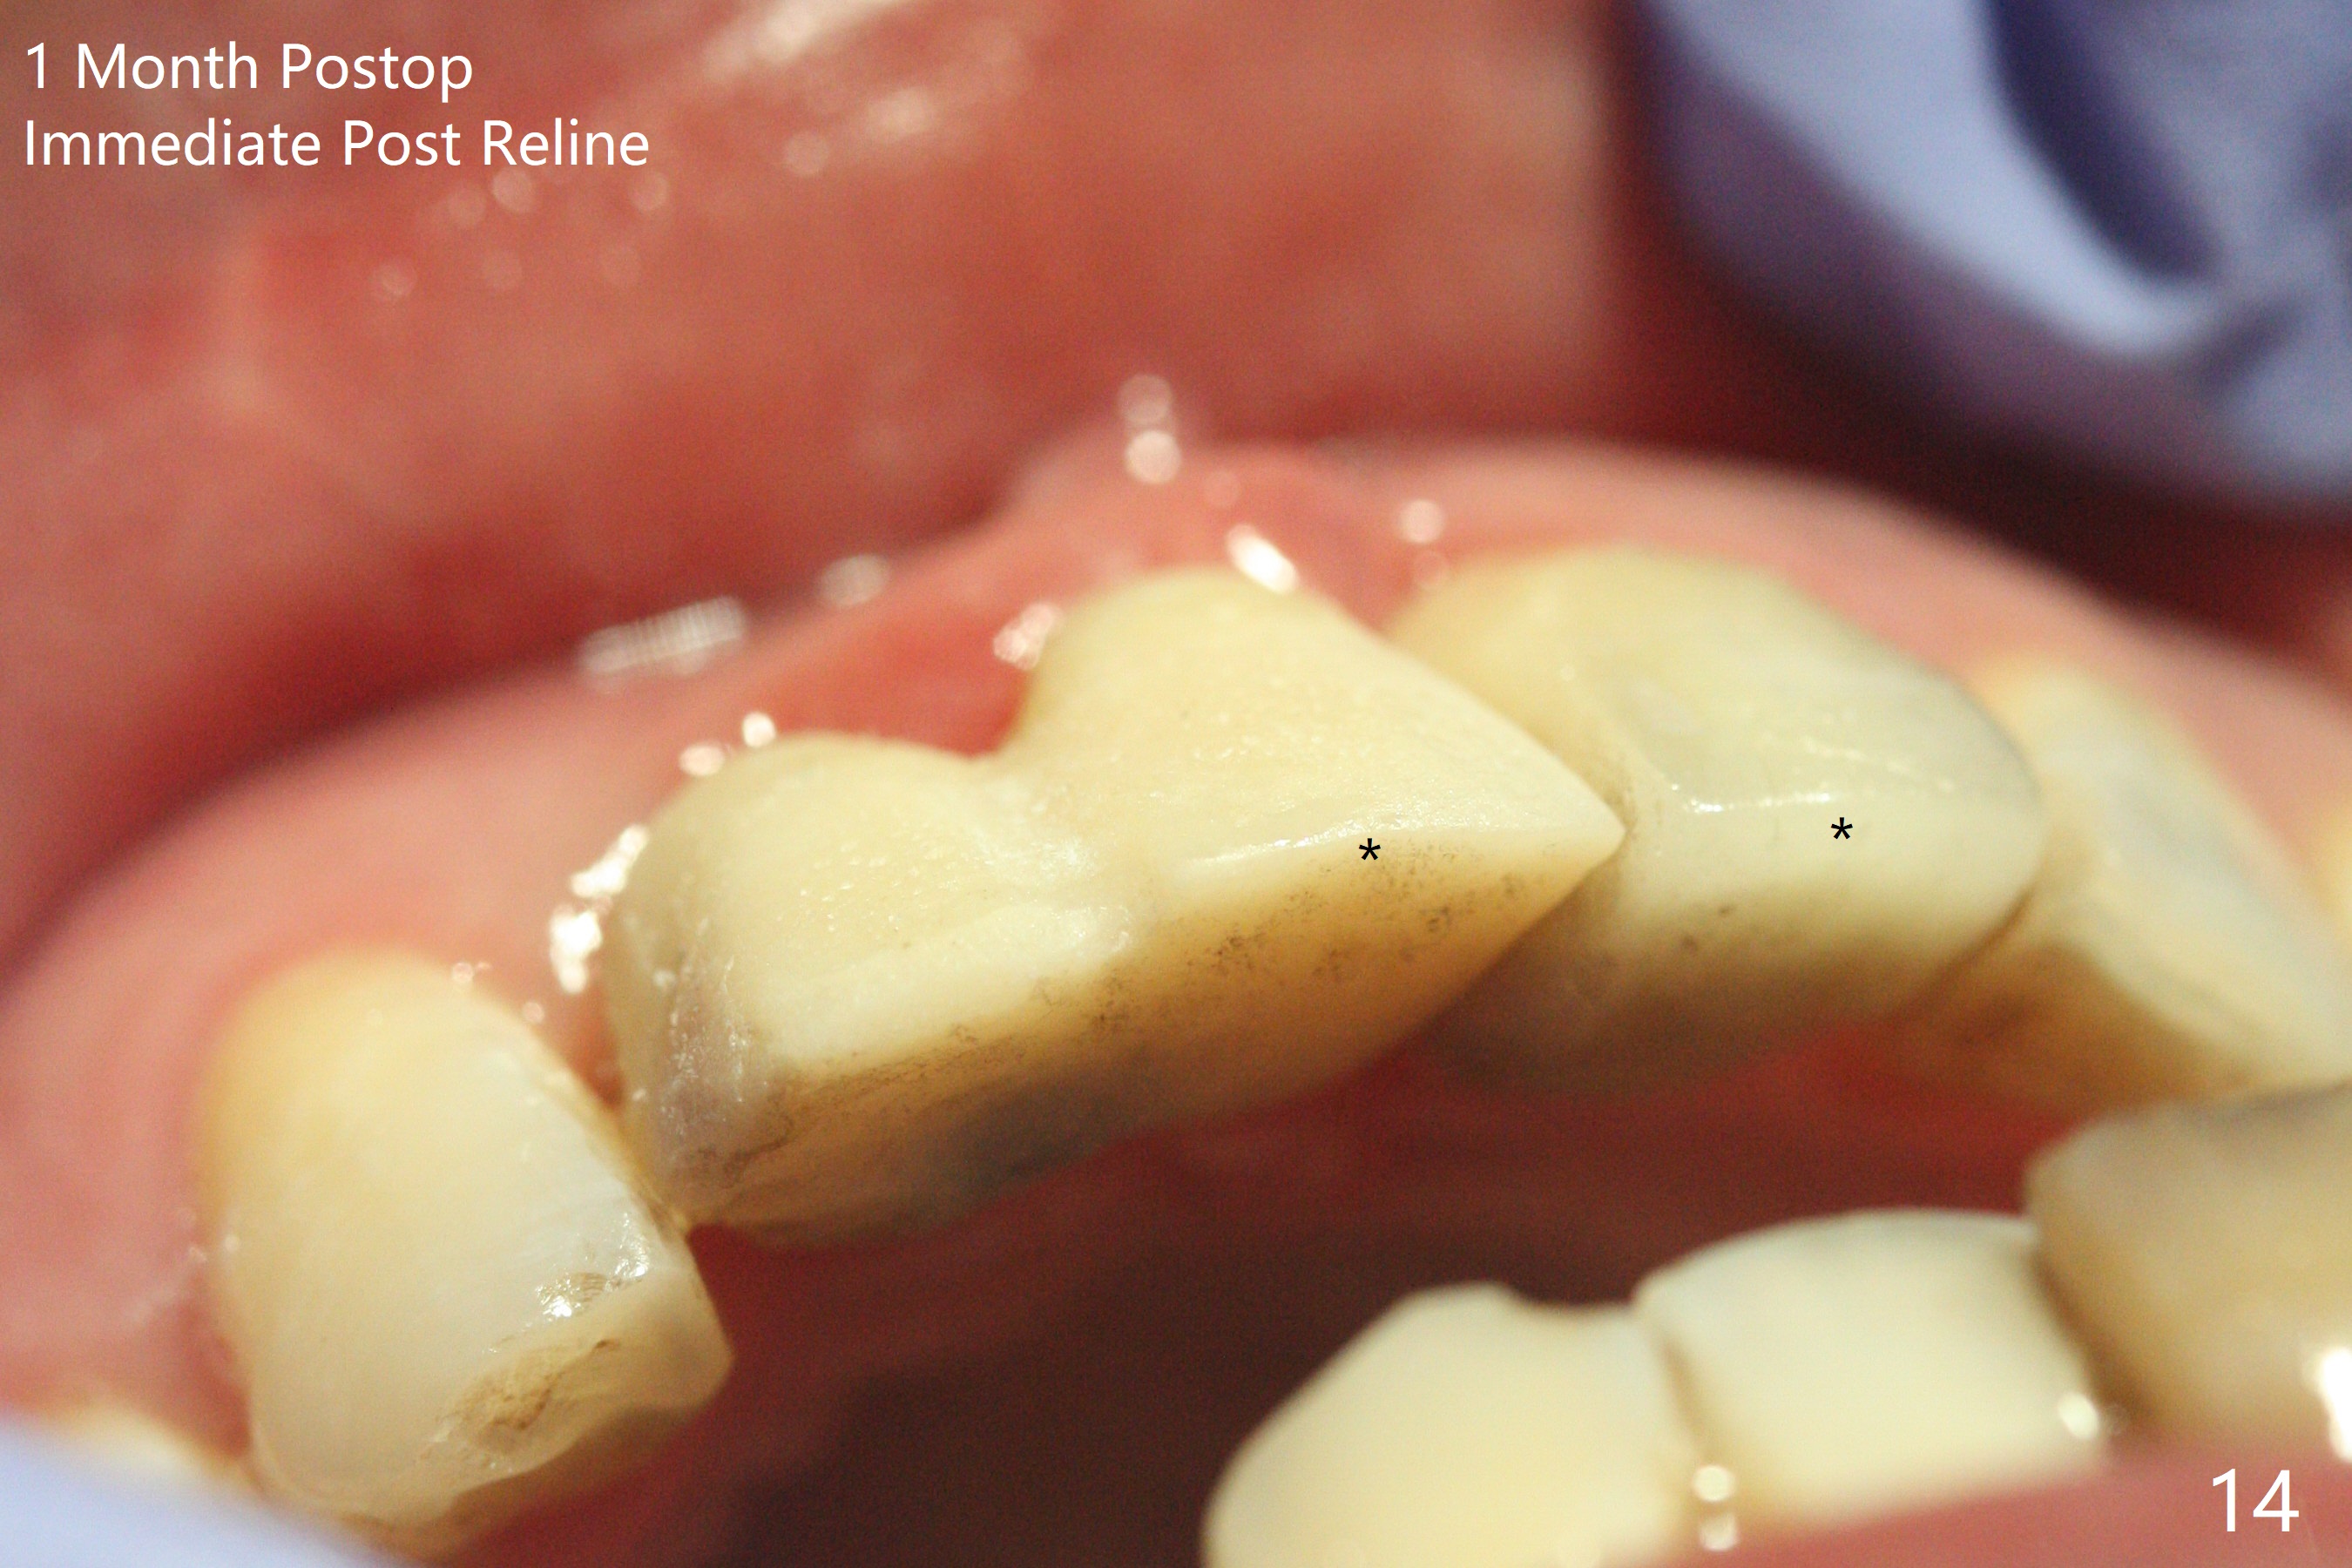

拆除部分桥发现:中,侧切牙牙龈红肿(图一),不利于切口和伤口愈合。不过还是在中切牙区切开,牙龈相当厚,有利于今后牙龈形成凹陷和乳头。坏消息是近远中距离太短,不利于植牙以及今后局部卫生维护,所以决定只在侧切牙种植(图二,三),完成钻洞后,颊侧根尖穿孔植骨,然后植入植体,即刻放置修复基台(图四 (*:牙龈乳头)),暴露基台牙龈缘,制作临时悬臂桥 (图五),两个中切牙牙冠长度差不多,插入临时桥时颊侧牙龈乳头基本形成(图六:*),缝合前颊侧,腭侧牙龈瓣下放置粘性骨块(图七,八:* )和PRF膜(图七:^)。最后使用牙周敷料。但愿术后牙龈炎症消失,形成良好牙龈乳头和pontic concavity。 其实由于口腔卫生习惯,术后十七天颊侧牙龈仍红肿(图九),而腭侧正常。如果口腔卫生改善而红肿依然存在,让实验室制作临时桥。术后一个月颊侧牙龈红肿好些(图十),好像骨粉丢失少许,可能与水枪使用有关。右上1牙冠显得太短(*)。也太肥大,因为右上1切缘太颊侧,与左上1对比(图十一:*)。由于颊侧牙龈(图十二:B)术中推向颊侧,与腭侧(P)牙龈之间放置大量粘性骨粉,术后一个月骨粉(<)形成牙龈,形成凹陷。颊侧萎缩不再明显了。右上1牙冠颈部多加些树脂,牙齿就显得长的多(图十三:箭头)。与侧切牙之间颈部故意留下间隙(*),让牙龈入位(空箭头),形成龈乳头。当右上1临时牙冠切缘(图十四:*)移到腭侧,外形改观不少。下次改善侧切牙唇侧。术后两个月三个星期牙龈红肿好像减轻,牙龈没有进入切牙间隙,干脆用树脂关闭(图十五:> <)。下次减少侧切牙切缘(^),适当增加中切牙长度(上提牙龈)。术后3.5个月植体好像整合,基台完全就位(图十六)。术后3.5个月Pontic凹陷形成,但是1,2之间龈乳头始终无法形成(图十七)。以后类似病例应该多种植一个。此例草率取模,可能需要临时粘固,观察植体近中颊侧所谓瘘道,必要刮治。由于比色不佳,需要实验室颜色更改,病人强化卫生,术后七个月,永久性牙冠粘固前,局部牙龈健康(图十八)。